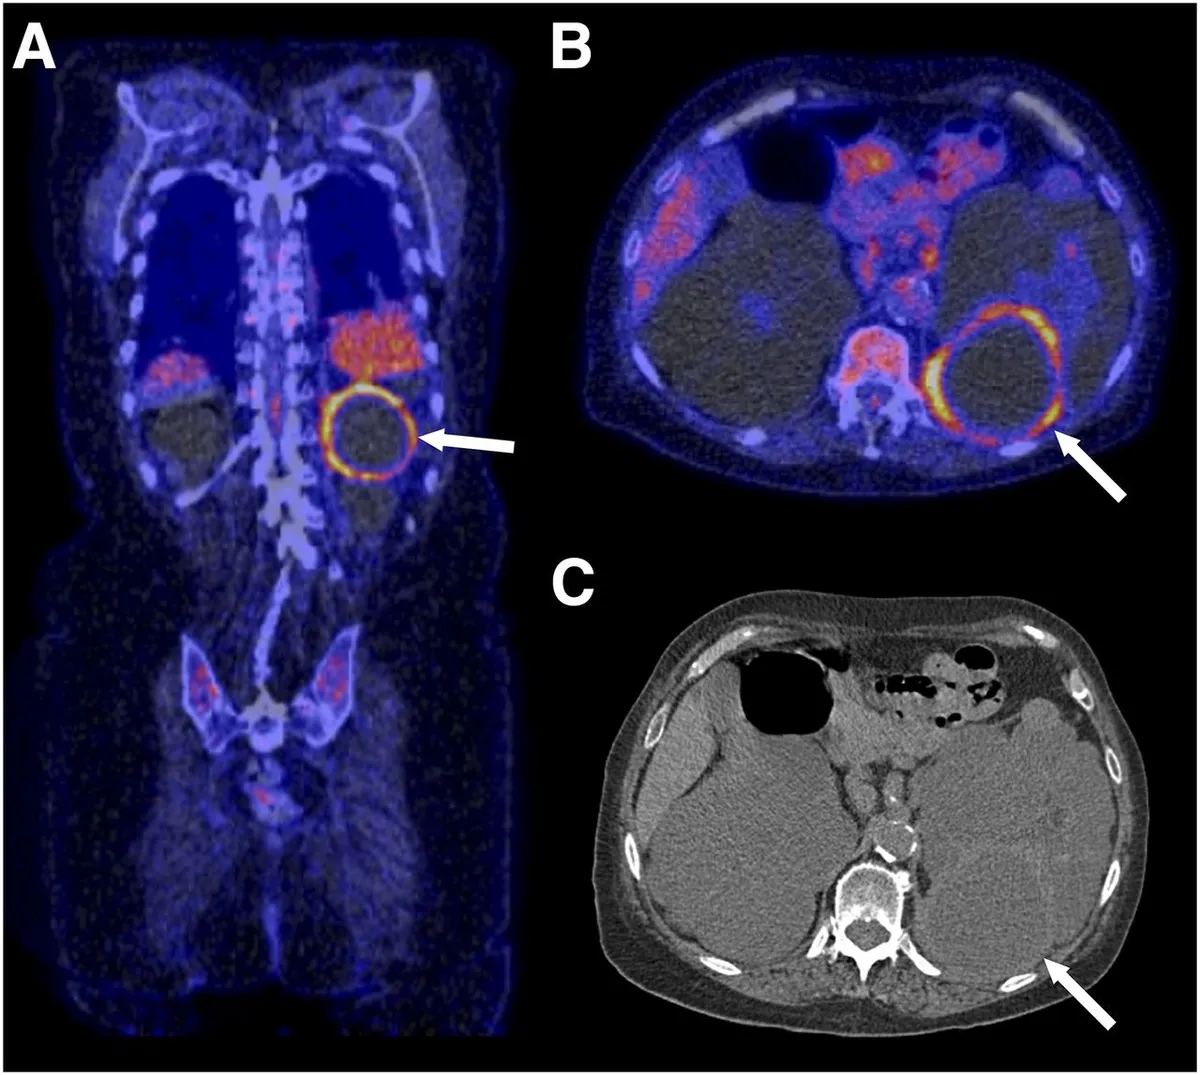

Uso do Tolvaptan na DRPAD: O Que falam nas Novas Diretrizes KDIGO 2025?

As novas diretrizes KDIGO para a Doença Renal Policística Autossômica Dominante (DRPAD) atualizam os critérios de elegibilidade para o uso de tolvaptana, com ênfase na estratificação do risco de progressão rápida. O documento reforça a individualização da terapia com base em subclassificação por imagem (Mayo Clinic) e função renal. A incorporação prática dessas recomendações pode otimizar o manejo e retardar a progressão da DRC nesses pacientes.